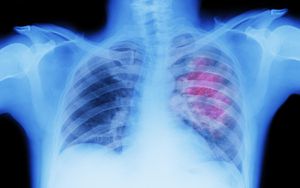

De otro lado, cabe destacar que los ministros de Sanidad (salud) de la Unión Europea (UE) ampliaron su recomendación de detección precoz, que ya incluía el cáncer de mama, cervical y colorrectal, a los de pulmón, próstata y gástricos para reducir la mortalidad en pacientes oncológicos y reducir la incidencia de los cánceres invasivos.